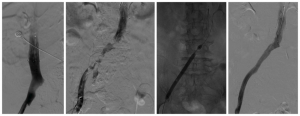

【一院·技术】下肢肿胀险截肢 元凶竟是“股青肿”,济宁市第一人民医院血管外科成功为患者取栓保肢

近日,济宁市第一人民医院血管外科深夜急症收治了一位下肢肿胀的...